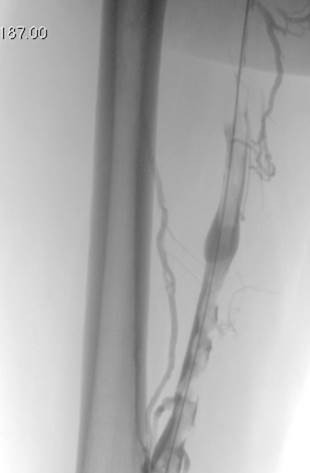

Eliminación razonable del trombo en las venas ilíacas tras una sola pasada del catéter DVX de AngioJet (25 mg de tPA en 250 cc de solución salina normal).

Venograma final tras la aspiración con catéter grande y tratamiento de la estenosis subyacente (debido a la compresión extrínseca del tumor) con un stent de 16 mm con el balón inflado a 12 mm.

Tiempo total: <90 minutos. Flujo interno perfecto de la parte posterior de la rodilla a la vena cava inferior (VCI).